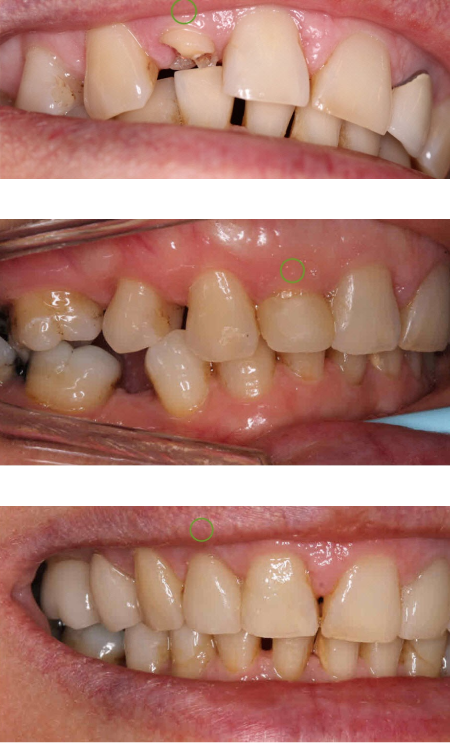

Changes in bite position with comprehensive treatment

When there is insufficient space to restore teeth

Opening the bite position provides a more stable

position also protecting the front teeth

Original bite position

Opened bite with upper restorations